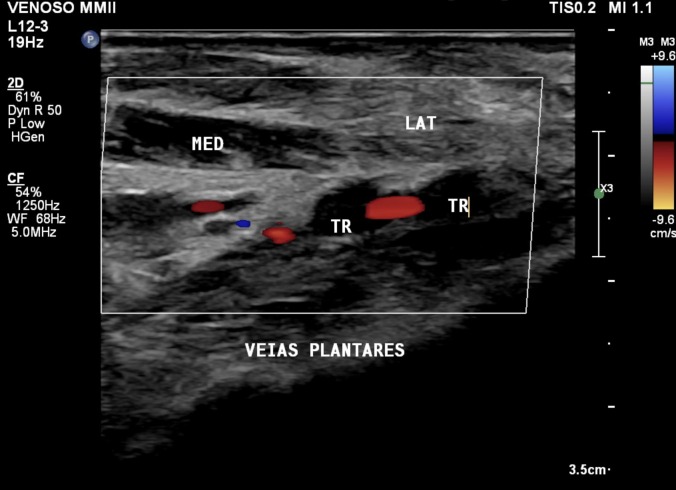

Plantar vein thrombosis is a vascular disease that affects the medial and/or lateral plantar veins. Its clinical manifestations are generally non-specific. However, it usually presents with pain in the plantar region, edema, and difficulty walking. The disease predominantly affects middle-aged females and is idiopathic in the majority of cases. The most commonly associated risk factors are recent surgical procedures, cancer, use of oral contraceptives, local trauma, and genetic disorders, such as hereditary thrombophilia. The gold standard diagnostic test is vascular ultrasound, evaluating venous compressibility. We report a case of venous thrombosis of the lateral plantar vein diagnosed with vascular ultrasound.